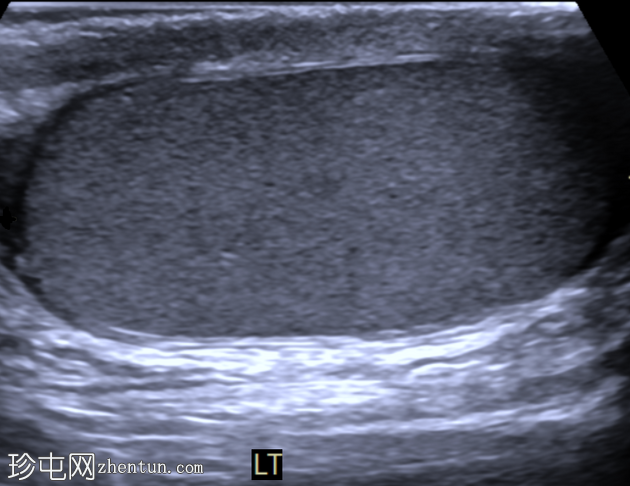

睾丸混合性生殖细胞瘤

右侧睾丸肿块,伴间歇性疼痛4个月。

年龄:30岁

性别:男

超声检查

横切面

右侧睾丸内可见一大小约3.0 x 5.0 cm的异质性分叶状低回声肿块。肿块内未见囊性区域或钙化。彩色多普勒超声检查显示肿块内血流丰富。左侧睾丸正常。